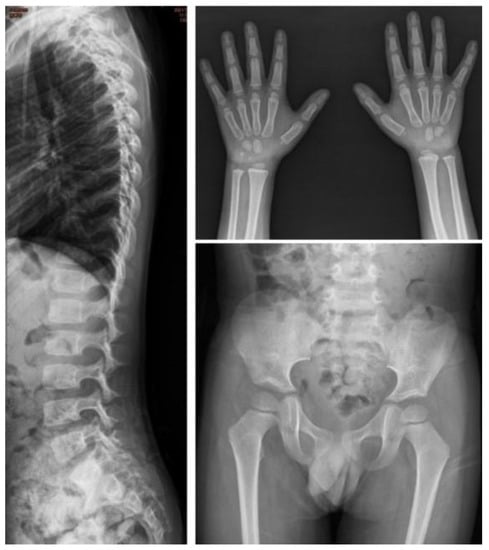

| I-1 | M | c.254C > T, p.A85V | — | — | Baseline | 0.4 | 0.83 | 78.58 | 11.59 | 12.36 | 0.25 | Normal | Normal | Normal | Normal | Normal |

| Follow-up | 3.9 | 1.24 | 35.42 | 0.77 | 25.75 | 4.46 | Normal | Normal | Normal | Normal | Normal | |||||